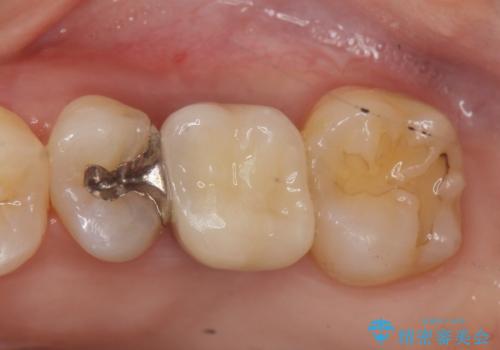

- 他院での矯正治療中、欠損した左上奥歯のインプラント治療を希望され来院されました。

最終的な歯の位置を矯正の担当医と綿密に相談しながら、インプラントの埋入部位を決定し治療にあたりました。

骨量が少なかったことから、上顎洞内へのソケットリフト方をインプラント埋入と同時に施行しています。

- 51.4万円(ストローマンインプラント・ソケットリフト・仮歯・カスタムアバットメント・ジルコニアクラウン)費用は治療当時の料金となります